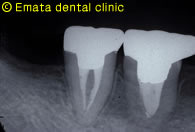

右上の虫歯が大きく、また右下の奥歯が根の病気が大きく抜歯になりました。 親知らずや内側に倒れた不必要になった歯があったので移植をおこないました。